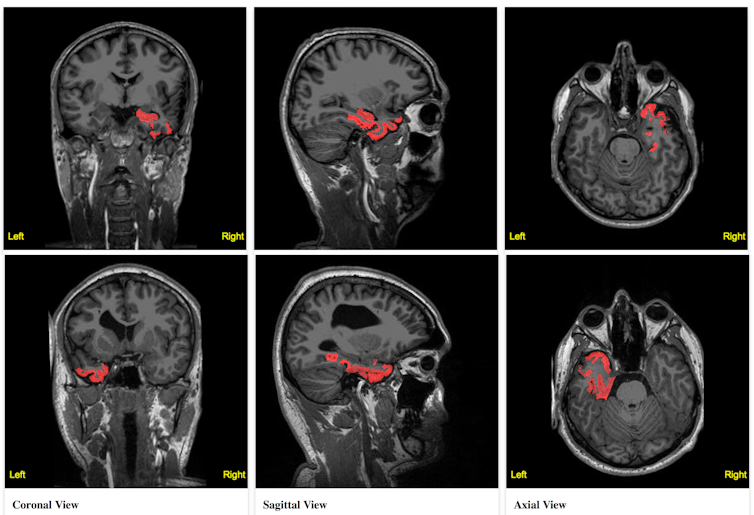

Un exemple concerne le traitement chirurgical de patients atteints d’épilepsie résistante aux médicaments. La personne hospitalisée se voit implanter des électrodes afin de réaliser un électroencéphalogramme enregistrant son activité cérébrale durant les crises. Ces données sont censées permettre d’identifier les zones à l’origine de son épilepsie, qui seront traitées chirurgicalement.

Le problème est qu’il peut parfois s’avérer difficile d’intégrer toutes les données et informations collectées, et d’en tirer des informations claires. La création d’un modèle de réseau cérébral basé sur une IRM du cerveau du malade permettrait de lever cette ambiguïté. Grâce à elle, il deviendrait en effet possible d’intégrer les informations disponibles de façon à mettre en évidence clairement des associations entre certaines données qui seraient difficiles à appréhender à l’œil nu : propagation de l’influx nerveux à travers une zone non monitorée, effet du placement des électrodes, etc.

Dans un premier temps, les données IRM seraient utilisées pour définir la forme et la connectivité du cerveau virtuel. On ajouterait ensuite sur ce modèle des électrodes (virtuelles elle aussi), aux mêmes positions que dans la réalité. Grâce à un modèle dynamique capable de simuler la transition entre les états relâchés et épileptiques, on pourrait alors régler finement les paramètres des différentes régions de ce cerveau virtuel : l’objectif serait que la simulation reproduise exactement les enregistrements réalisés sur le patient.

Une telle procédure permettrait d’identifier les régions les plus impliquées dans la survenue des crises, fournissant aux cliniciens qui vont intervenir des données complémentaires pour éclairer leurs décisions.

Cette approche a déjà permis d’obtenir des résultats encourageants durant des études pilotes. Elle est actuellement évaluée dans le cadre d’une étude clinique prospective au sein du projet EPINOV.